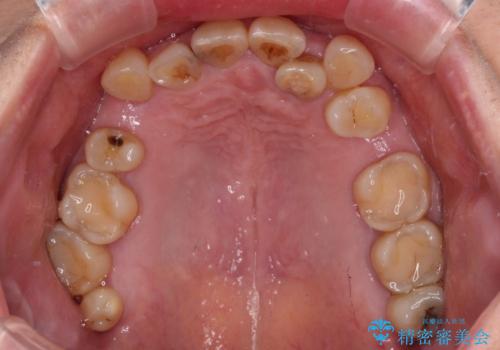

- 常に外れている下顎のブリッジと、前歯のデコボコと色を気にして来院された患者様です。

前歯のデコボコおよび奥歯の咬み合わせを改善するために、上顎左右の小臼歯を欠損スペースを利用して歯列を整え、矯正治療後に気になる上下前歯などをオールセラミッククラウンで美しく仕上げていくこととしました。